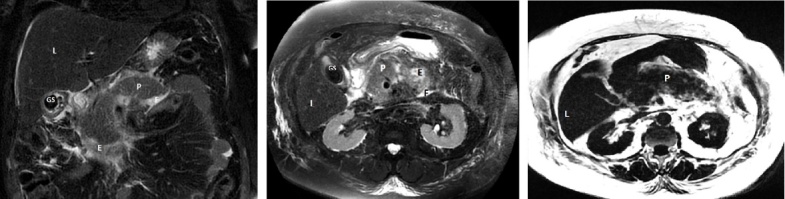

在胆道疾病中,胆结石的发病率在最近几年有所上升,仅在美国,就有约 6% 的男性和 9% 的女性患有胆结石。在西方国家,10%-20% 的成年人患有胆石症。虽然年龄的增长是胆结石形成的一个主要风险因素,但晚近的研究表明,胆结石的出现与症状出现的年龄下降有关。因此,我们面对的是一个表现为疼痛,有时还伴有功能障碍的年轻群体。根据统计分析,胆结石对美国等高度工业化国家的经济影响每年高达 65 亿美元。在这种情况下,适当的干预时机就成为一个重要的关注因素。本综述使用了 28 篇文章和专业文献。文章的选择以关键词为基础,关注超声波、CT 和核磁共振成像等影像学检查对胆石症患者诊断的有效性。由于无法对影像学检查技术进行直接比较,我们尝试确定每种影像学评估的敏感性和特异性。比较分析表明,P Kruskal-Wallis

From the category of biliary disease, gallstones registered an increase during the last years, approximately 6% of men and 9% of women being affected by the pathology in the United States only. In western countries between 10-20% of the adult population is suffering from cholelithiasis. Although increasing age is a major risk factor for their formation, late studies correlate gallstones appearance with an age decrease for the onset of symptoms. We therefore face a younger population manifesting pain and sometimes functional disability. In accordance with statistical analysis, the economic impact of gallstones in highly industrialized countries such as United States produces costs of up to 6.5 billion dollars annually. In this context, the appropriate timing for intervention becomes a factor of major interest. The present review uses 28 articles and specialized literature. Article selection was based on keywords and followed the effectiveness of imaging investigation such as ultrasound, CT and MRI for patients diagnosed with cholelithiasis. Since a direct comparison between the imaging investigation techniques is not concluding we have tried to establish the sensitivity and specificity offered by each imaging assessment. The comparative analysis revealed a p Kruskal-Wallis <0.001 for sensitivity and p Kruskal-Wallis=0.474 for specificity.